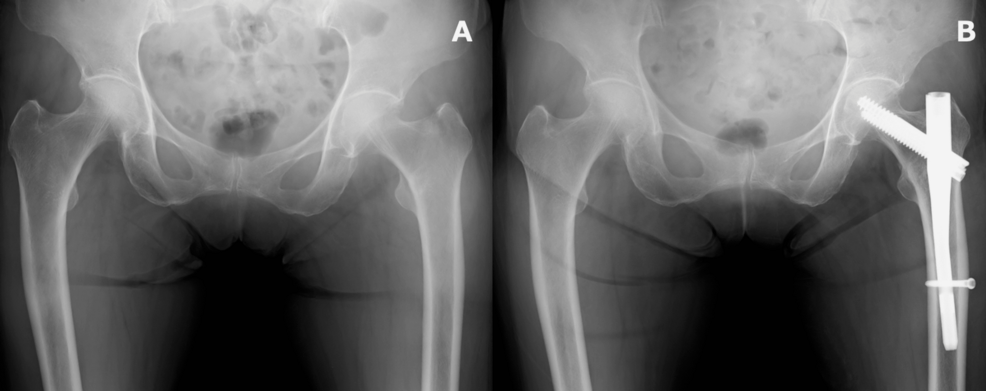

Imagine a future where hip replacement revision surgeries are increasingly driven not by implant wear or infection, but by fractures *around* the implant itself. This isn’t science fiction. A recent case study published in Cureus details a second non-prosthetic peri-implant femoral fracture (PIFF) following plating for a primary PIFF after a trochanteric femoral fracture – a complex scenario highlighting a potentially growing challenge in orthopedic surgery. This isn’t an isolated incident; the increasing prevalence of these fractures, particularly in an aging population with higher rates of osteoporosis and complex medical histories, demands a proactive re-evaluation of surgical techniques and implant designs.

A peri-implant fracture, as the name suggests, is a break in the bone surrounding a prosthetic implant, rather than a failure of the implant itself. These fractures are becoming more common, especially after hip replacement surgery. The Cureus case report underscores a particularly concerning trend: the occurrence of *secondary* PIFFs after initial attempts at fixation. This suggests that standard plating techniques may not always provide sufficient long-term stability, especially in patients with compromised bone quality. The initial fracture, often a trochanteric fracture, weakens the bone stock, and subsequent stress can lead to further fractures around the implant.

Surgeons may need to consider more extensive revision procedures, such as femoral bone grafting or the use of longer stems to bypass the fractured area. In some cases, a complete femoral reconstruction may be necessary. The Cureus case report highlights the potential for failure even with initial plating, suggesting that more aggressive revision strategies may be warranted in certain situations.